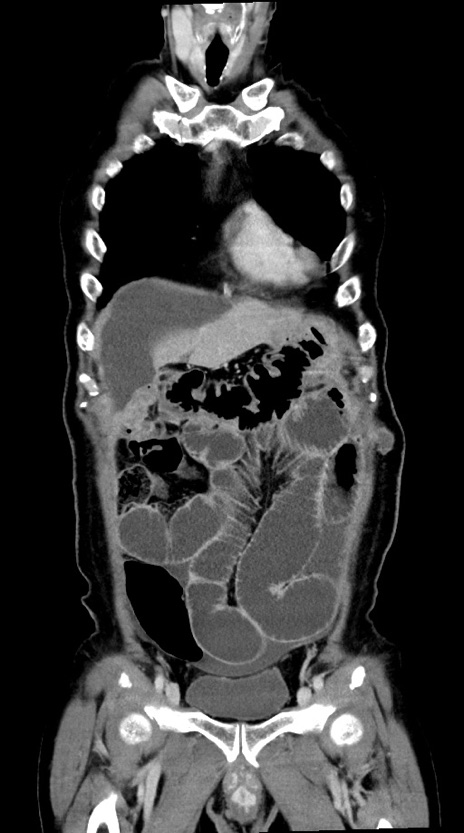

症例28(冠状断像)

【症例】60歳代男性

【主訴】嘔吐

【現病歴】胃癌にて胃全摘後。食思不振が悪化し、夜中に嘔吐することがある。

【既往歴】胃癌、胃全摘、脾摘、胆摘後

【データ】WBC 5900、CRP 10.56